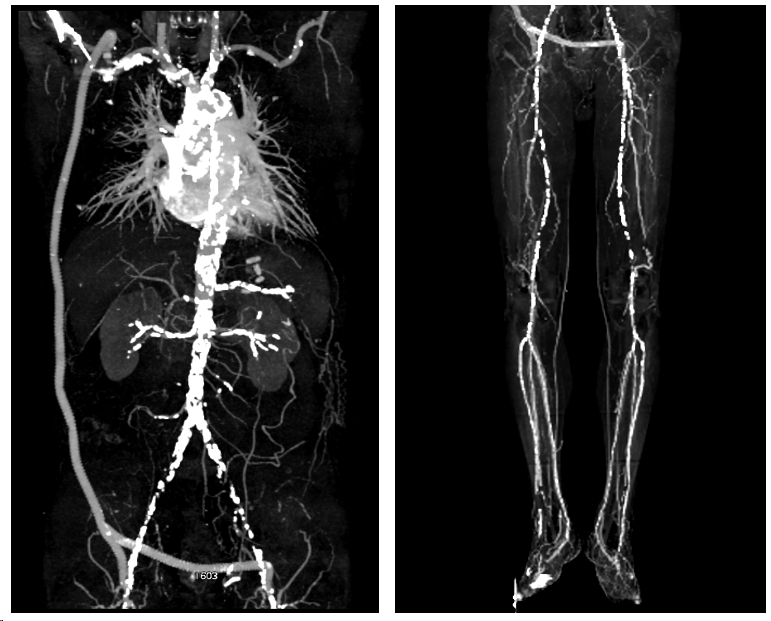

辅助检查:胸部+上下腹部+双下肢动脉CTA提示:右锁骨下动脉-股动脉-股动脉人工血管旁路通畅,双侧股动脉多发闭塞,双侧腘动脉、膝下动脉通畅(图2)。

(图2)术前CT重建